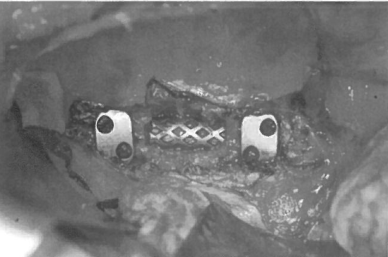

图1 植骨后安置锁环,前方螺栓与后方螺栓保持距离

锁环的安置

选择合适的锁环安置在椎体上正确的位置(图1)。中央的齿状结构可以使连接更为牢固。